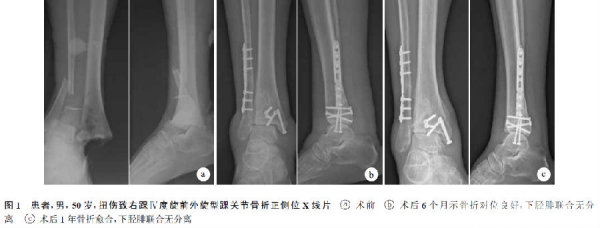

术后患者切口均Ⅰ期愈合,无相关并发症发生。32例均获随访,随访时间12~24个月,平均15个月。X线片复查示骨折均愈合,愈合时间10~14周,平均11.2周。随访期间未见下胫腓联合分离现象(图1)。末次随访时,按照美国矫形足踝协会(AOFAS)踝关节-后足评分为61~98分,平均88.4分;获优13例,良15例,一般4例,优良率87.5%。